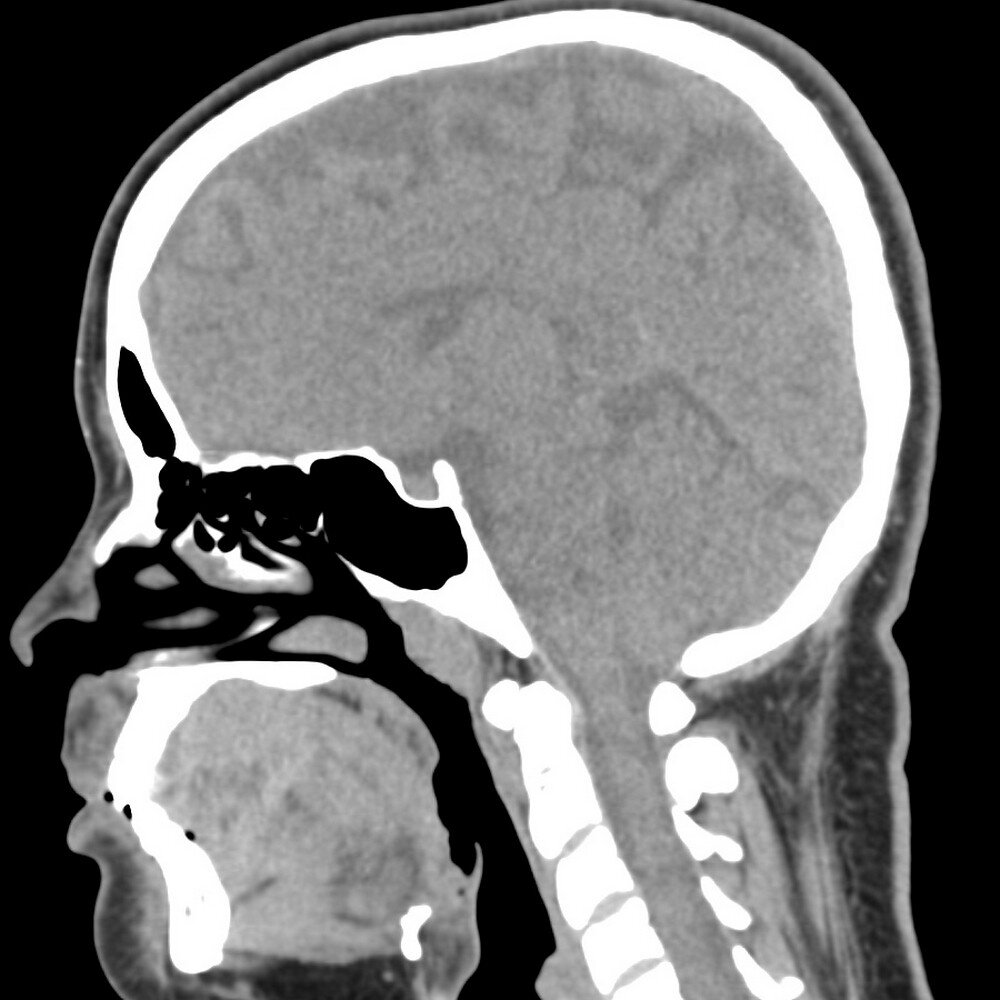

КТ головного мозга (полное название - мультиспиральная компьютерная томография головного мозга) - это неинвазивное, рентгенологическое сканирование костных и мягких структур головы. В процессе обследования компьютерный томограф хорошо визуализирует черепные пластины и мозговые доли. Если врач применяет специальную ангиопрограмму, дополнительно можно воссоздать анатомическую картину сосудистой сети. Результатом диагностики станут 3Д снимки и рентгенологическое заключения с деланным описание всех выявленных патологий. МСКТ головного мозга позволяет быстро и точно устанавливать факт наличия черепных повреждений, кровоизлияний и новообразований разнообразного происхождения. Это может быть крайне важно в экстренных ситуациях, когда пациент находится в критическом положении, и врачам нужно принимать решении о тактике лечения.

КАК ДЕЛАЮТ КТ ГОЛОВНОГО МОЗГА

Современная МСКТ головного мозга в сравнении с ранними моделями КТ-аппаратов оказывает небольшую лучевую нагрузку на организм. Во время процедуры датчики аппарата для компьютерной диагностики послойно сканируют головной мозг и кости черепа по срезам, передавая их изображение на монитор. Современные томографы делают от 4 срезов до 640 за один оборот. Затем компьютер объединяет все эти сканы в 3D-изображение, которое можно рассмотреть в плоскости 360 градусов. Это способствует получению точной информации о состоянии органов в виде их трехмерной проекции. В медицинских центрах обследование головы на компьютерном томографе можно осуществить по нескольким протоколам (нативно, с контрастом, в ангиорежиме).

По окончании компьютерной томографии рентгенолог проводит полную расшифровку томограммы. Он сравнивает итоговые снимки с нормативными показателями развития мозга, описывает все затемненные зоны на изображении участков головного мозга и выявляет признаки опухолей и ишемического инсульта. Специалист в своем заключении описывает характер патологий, а окончательный диагноз устанавливает лечащий врач. Поэтому после КТ головы пациент всегда получает рекомендацию записаться на прием к лечащему врачу, чтобы завершить процедуру диагностики и начать адекватную терапию в случае необходимости.

Поскольку головной мозг человека на 80% состоит из воды, его ткани хорошо и четко видны на МРТ снимках. Компьютерная томография головного мозга хуже, чем магнитно-резонансная томография, визуализирует вещество и кору головного мозга, зато прекрасным образом отображает особенности строения костных структур черепа.